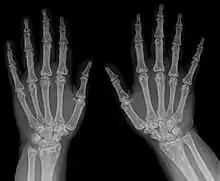

Diagnostic method | X-ray, ultrasound[3] |

The diagnosis of this condition can be ascertained via several techniques one such method is genetic testing, as well as:[2][3]

- X-ray

- Ultrasound

- Histological test